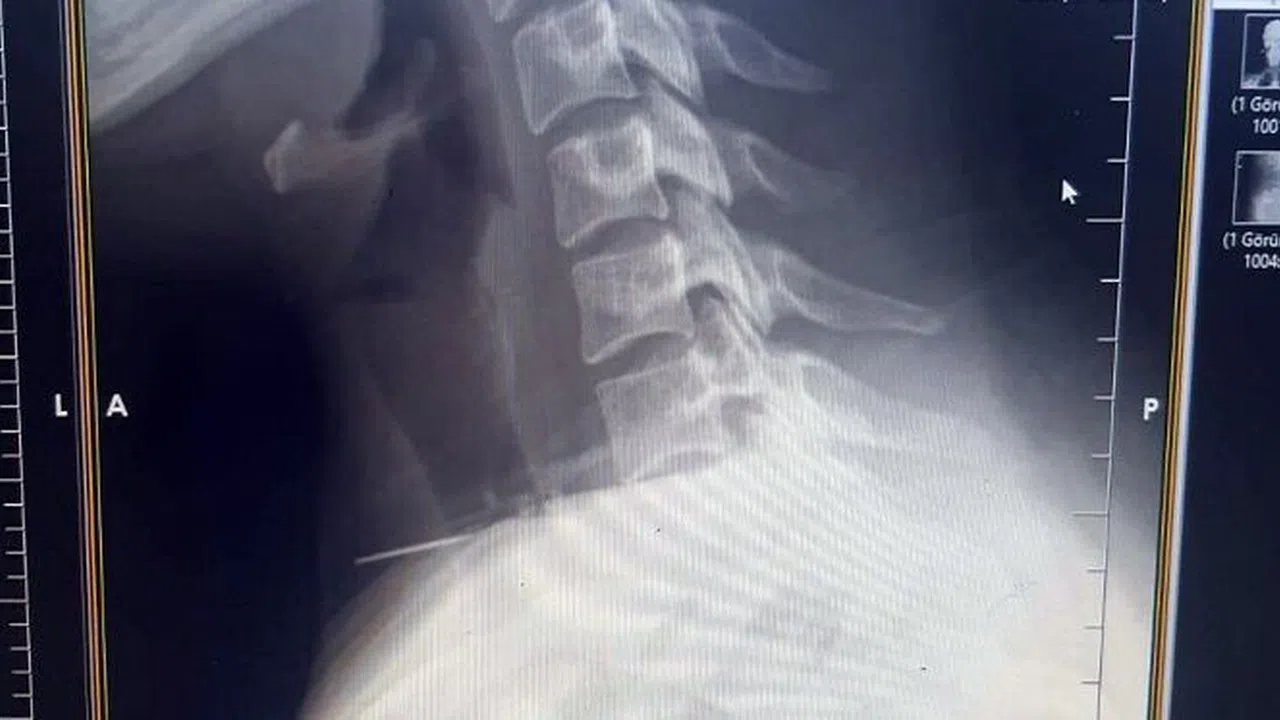

Edinilen bilgiye göre olay, Şanlıurfa’nın Birecik ilçesinde yaşandı. Boğazına dikiş iğnesi saplanan 25 yaşındaki Z.İ., Birecik Devlet Hastanesine başvurdu. Radyolojik incelemeler ve klinik değerlendirmeler sonucunda, 3 santimetrelik iğnenin boğaz bölgesinin derinliklerine doğru ilerlediği tespit edildi. İğne, yaklaşık 1 saat süren ameliyatla çıkarıldı. Ameliyat sonrası süreci sorunsuz atlatan hasta taburcu edildi. Ameliyatı gerçekleştiren Birecik Devlet Hastanesi Kulak Burun Boğaz ve Baş Boyun Cerrahisi Uzmanı Dr. Rafet Yıldırım, boynuna iğne saplanan kadın hastayı başarılı bir operasyonla sağlığına kavuşturduklarını söyledi.

Şanlıurfa’nın Birecik ilçesinde bir kadının boğazına saplanan iğne, ameliyatla çıkarıldı.